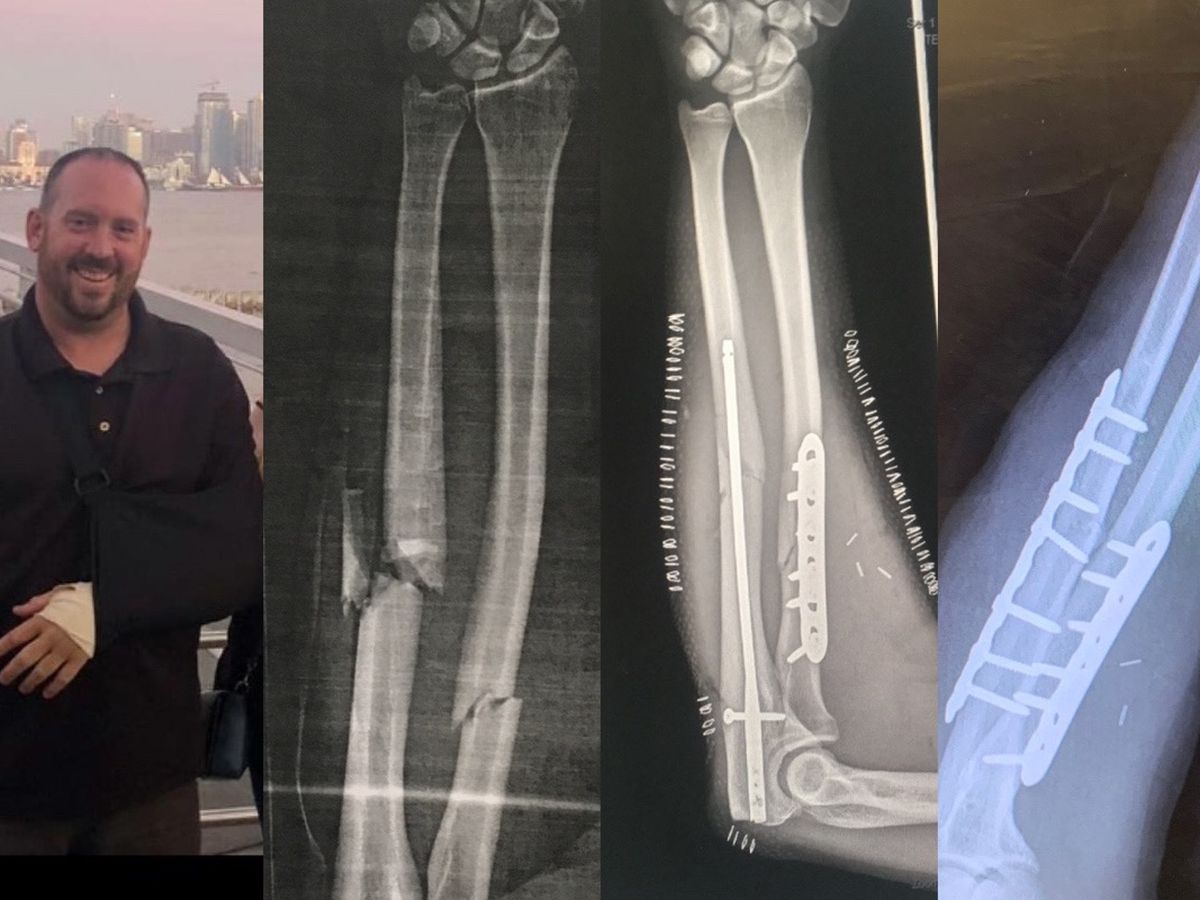

Unfortunately, I took the brunt of the hit and knew immediately that my left forearm arm was broken. I was brought back to the shore by my friends and transported to the hospital. That is where I found out later that I had two fractures in my forearm, 7 broken ribs, and a pneumothorax (collapsed lung) of my left lung. Due to the fracture of my arm and being in the salt water in the bay, it was mandatory for me to spend four days in the hospital to receive IV antibiotics.

(Initial image of broken arm)

(Initial image of broken arm)

(Initial repair of broken arm)

(Initial repair of broken arm)

Now fast forward to June and I find out one of the bones in my arm (ulnar) did not heal and I had to undergo another surgery to repair the broken bone. The most recent surgery required removal of some of the hardware in my arm, and replacing it with a bone graft from my hip and new metal hardware to restart the healing process. This also required taking a few weeks off of work to recover. I now have two plates and 14 screws in my arm and have had hundreds of staples and stitches during the surgeries and am still trying to fully recover so that I can get cleared for full work status.

(The bone break is very clear on the right, 9 months later)

(The bone break is very clear on the right, 9 months later)

(Extensive damage to the hull that is not worth repairing. Seadoo went to the trash.)Unfortunately, I took the brunt of the hit and knew immediately that my left forearm arm was broken. I was brought back to the shore by my friends and transported to the hospital. That is where I found out later that I had two fractures in my forearm, 7 broken ribs, and a pneumothorax (collapsed lung) of my left lung. Due to the fracture of my arm and being in the salt water in the bay, it was mandatory for me to spend four days in the hospital to receive IV antibiotics.

(Initial image of broken arm)

(Initial image of broken arm) (Initial repair of broken arm)

(Initial repair of broken arm)I was lucky enough to have some friends and an amazing sister there to take care of me, and my stuff that was left at the bay. My sister stayed with me for over a week to make sure I was OK physically and able to start my recovery, which took about 4 weeks to get back to work.

(Amazing sister that helped me out! Took her out for dinner before she had to fly home)Now fast forward to June and I find out one of the bones in my arm (ulnar) did not heal and I had to undergo another surgery to repair the broken bone. The most recent surgery required removal of some of the hardware in my arm, and replacing it with a bone graft from my hip and new metal hardware to restart the healing process. This also required taking a few weeks off of work to recover. I now have two plates and 14 screws in my arm and have had hundreds of staples and stitches during the surgeries and am still trying to fully recover so that I can get cleared for full work status.

(The bone break is very clear on the right, 9 months later)